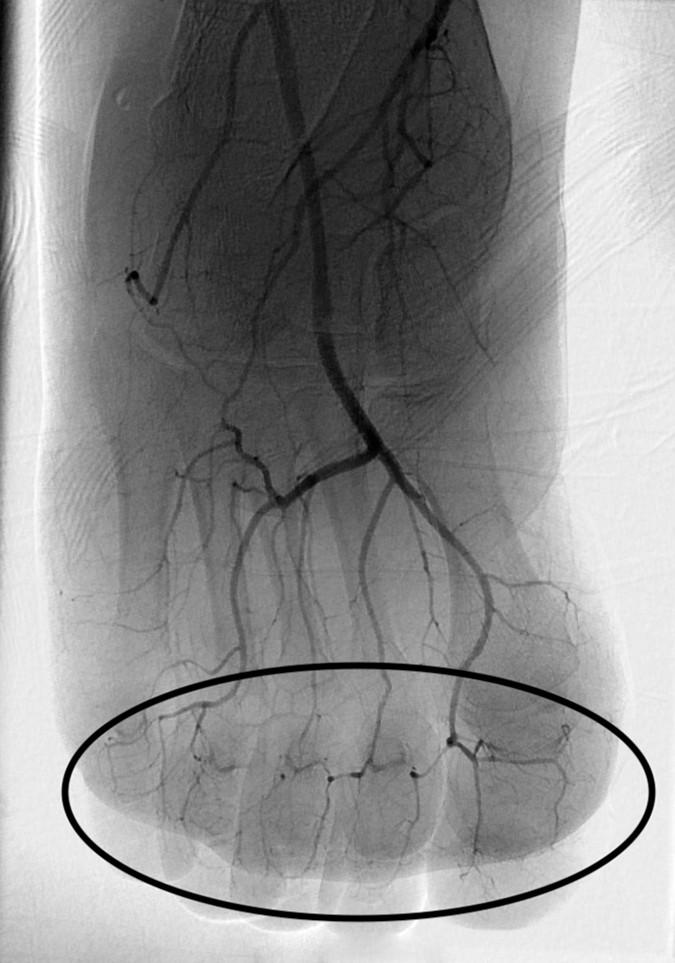

Both digital subtraction angiography (DSA) and triple-phase bone scan were utilized for initial imaging evaluation of patients with severe frostbite injuries.

Lee and Higgins' analyzed series included 209 patients with 1109 digits at risk of amputation treated with IA or IV tPA--116 and 77 patients, respectively. A total 926 at-risk digits were treated with IA tPA and resulted in amputation of 222 digits, for a salvage rate of 76%. Twenty-four of 63 patients underwent amputation after IV tPA, resulting in a 62% salvage rate.